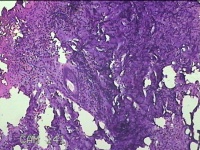

肛周脓壁组织

性别

男

年龄

46岁

临床诊断

1.肛周脓肿 2.混合痔 3.肛裂

一般病史

肛周疼痛2天。

标本名称

大体所见

灰白暗红色不规则碎组织2.2x0.3x0.2cm一块,表面糜烂,位面灰白暗红色,质软。

像良性病变,所提供图片不具有诊断价值。